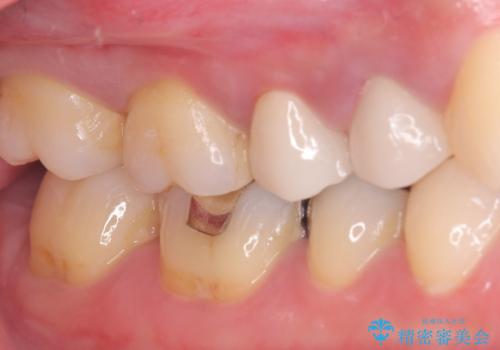

- 主訴:銀の詰め物を入れている歯が割れてしまった。

右上5番に保険適応のインレーが入っている歯がインレーを境に2つに割れてしまっていました。

露出した歯質には深いう蝕があり、一部神経を除去するもしくは全て神経を除去する可能性を説明し残存歯質量と破折リスクの観点からセラミッククラウンでの補綴修復しました。